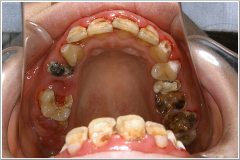

この状態では、まず歯の治療よりもその根源であるプラーク(汚れ)の除去だと判断し、文字通り腫れ物に触る思いで慎重に取り除いていきました。二日に分けてお掃除をしたのがこの写真です。

ところが実際には、むし歯は前歯よりも奥歯の方がひどかったのです。